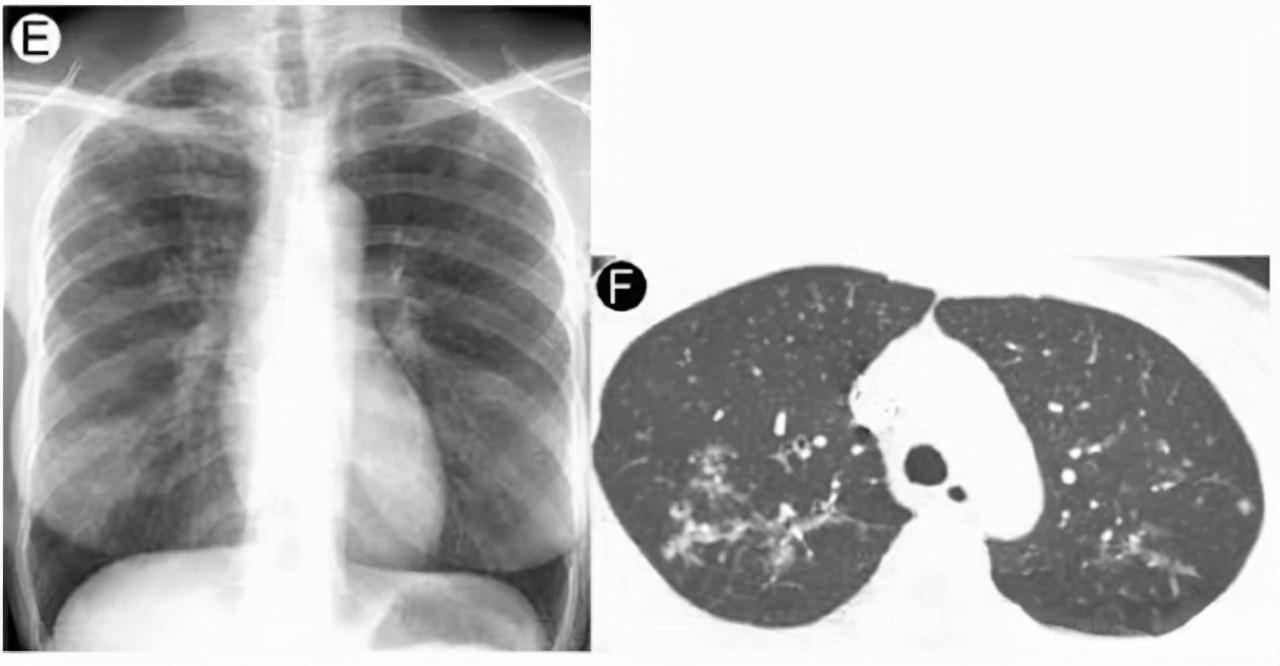

肺结节的诊断需要综合考虑多个因素。根据结节的密度,可以将其分为实性结节、部分实性结节和磨玻璃密度结节。其中,部分实性结节的恶性概率最高,其次是磨玻璃密度结节,实性结节的恶性概率相对较低。影像学检查是诊断肺结节的主要手段,胸部CT是最常用的方法,能够显示结节的大小、密度、形态和边缘等特征。

对于肺结节的处理,需要根据结节的大小、形态、生长速度以及患者的个体特征来制定随访策略。对于直径小于5毫米的实性结节,建议1年后随访;5-15毫米的结节应在3个月后进行随访观察;大于15毫米或表现出恶性CT征像的结节,则需要进一步检查明确诊断。